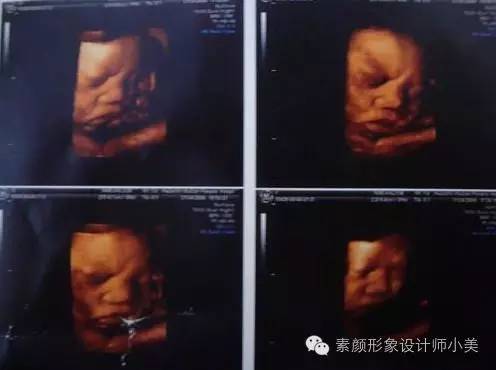

现在你的胎儿可能已经有3200克重了,身长也得有52厘米左右了。胎儿的头在你的骨盆腔内摇摆,周围有骨盆的骨架保护,很安全。这样也腾出了更多的地方长他的小胳膊、小腿、小屁股。很多胎儿这时头发已长得较长较多,大约有1-3厘米长,如果父母中某一方头发是自来卷的话,你的胎儿也很可能是个小卷毛头。